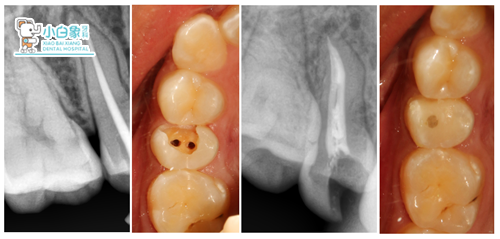

X线检查:根管内见高密度影欠填,根尖见低密度影。

治疗计划:15根管治疗+纤维桩+瓷睿刻全冠修复

治疗:15去除根管内充填材料及腐质,寻两根管,测根长19mm,M3根备,超声荡洗,隔湿干燥,热牙胶充填根管,在颊侧根管制备桩道,3M纤维桩粘结。